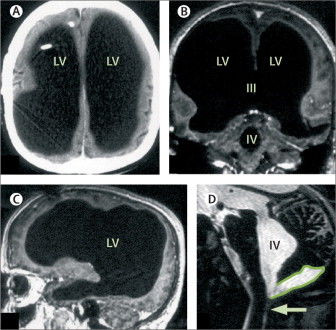

Bệnh nhân người Pháp phải nhập viện sau khi cảm thấy chân trái của mình yếu đi trong hai tuần. Trong quá trình chẩn đoán bệnh, ông được thực hiện nhiều xét nghiệm. Các bác sĩ đã vô cùng ngạc nhiên khi ảnh chụp não của não của bệnh nhân lại không phải não mà là một khoang chứa đầy chất lỏng khổng lồ.

Ảnh chụp não toàn chất lỏng của bệnh nhân.

Thế nhưng kết quả quét não đã khiến tất cả phải giật mình. Não bộ của ông đã sưng lên quá nhiều, chứa đầy dịch tủy, và thứ dịch ấy gần như đã thay thế toàn bộ khối óc, chỉ để lại một lớp vỏ não mỏng chứa các neuron thần kinh. Nói cách khác, người đàn ông này gần như không có não.

Việc chất lỏng lưu thông khắp não là bình thường. Tuy nhiên ở trường hợp này, thay vì được đưa vào hệ thống tuần hoàn, chất lỏng trong não người đàn ông này tích tụ lại. Cuối cùng, sự tích tụ chất lỏng chiếm hết không gian trong sọ, chỉ có một lượng siêu nhỏ là não thực sự.

Bệnh sử của người đàn ông cho thấy ông từng phải đặt một ống dẫn lưu vào đầu khi còn nhỏ để loại bỏ sự tích tụ chất lỏng trong não, hay còn gọi là bệnh não úng thủy. Ống dẫn lưu cuối cùng đã được cắt bỏ khi ở tuổi 14, nhưng ông luôn thấy tình trạng chân trái yếu và đi đứng không vững.